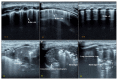

Results: We included 17 studies, reporting a total of 274 patients with M. pneumoniae, 30 with fungal infection and 213 with pulmonary tuberculosis (TB). Most of the studies on M. pneumoniae in children found a specific LUS pattern, mainly consolidated areas associated with diffuse B lines. The typical LUS pattern in TB consisted of consolidation and small subpleural nodes. Only one study on fungal disease reported LUS specific patterns (e.g., indicating "halo sign" or "reverse halo sign").

Conclusions: Considering the preliminary data, LUS appears to be a promising point-of-care tool, showing patterns of atypical pneumonia and TB which seem different from patterns characterizing common bacterial infection. The role of LUS in the diagnosis of fungal disease is still at an early stage of exploration. Large trials to investigate sonography in these lung infections are granted.